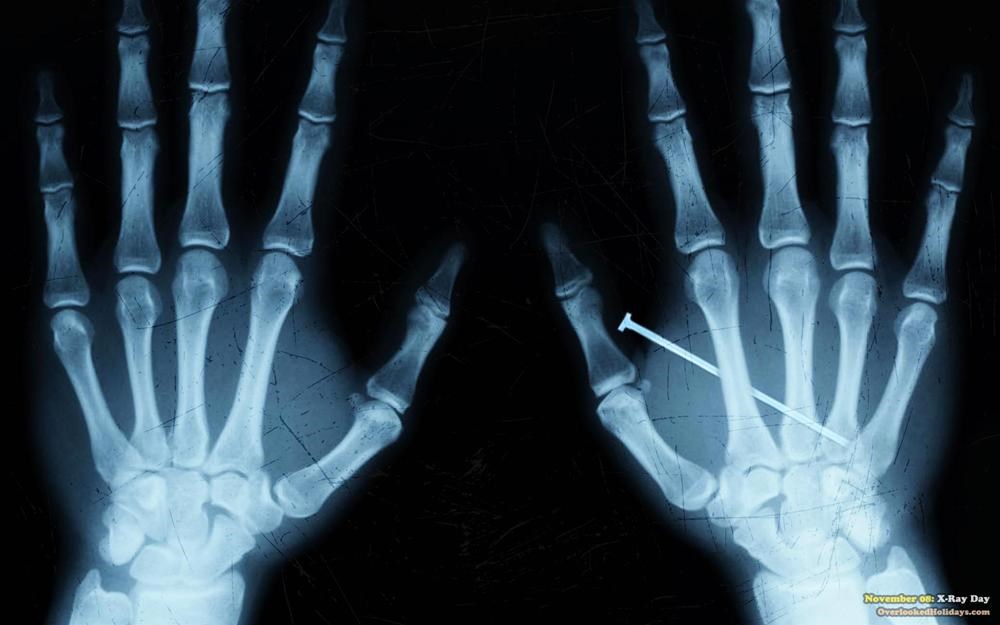

X ışınları

Alman fizikçi Wilhelm Roentgen, katot ışınlarıyla deney yaparken, floresan bir kartonun odanın karşısından parladığını gördü. Işın kaynağı ile ışığı yansıtan karton arasına beyaz bir perde koyarak ilk röntgeni çekti.